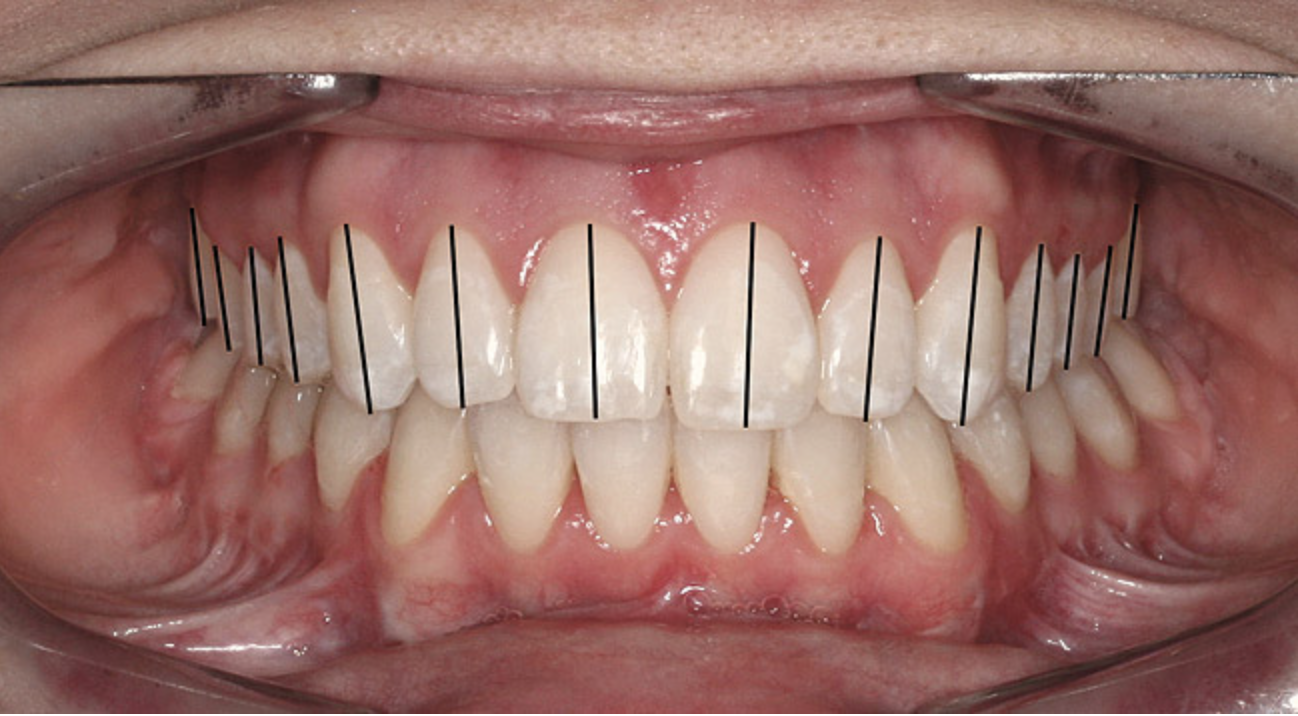

The dental midline can be improved within limits by restorative procedures. However, if orthodontic alignment is to be performed, the orthodontist plans treatment to ensure the position and vertical axis of the midline is harmonious with the facial esthetics (Figure 1).

Figure 1  Dental midlines should be as close to coincident as possible. Gingival height of maxillary lateral incisors should be even with a line between the gingival height of the central incisor and canine to 1.5 mm below that line.

Figure 1